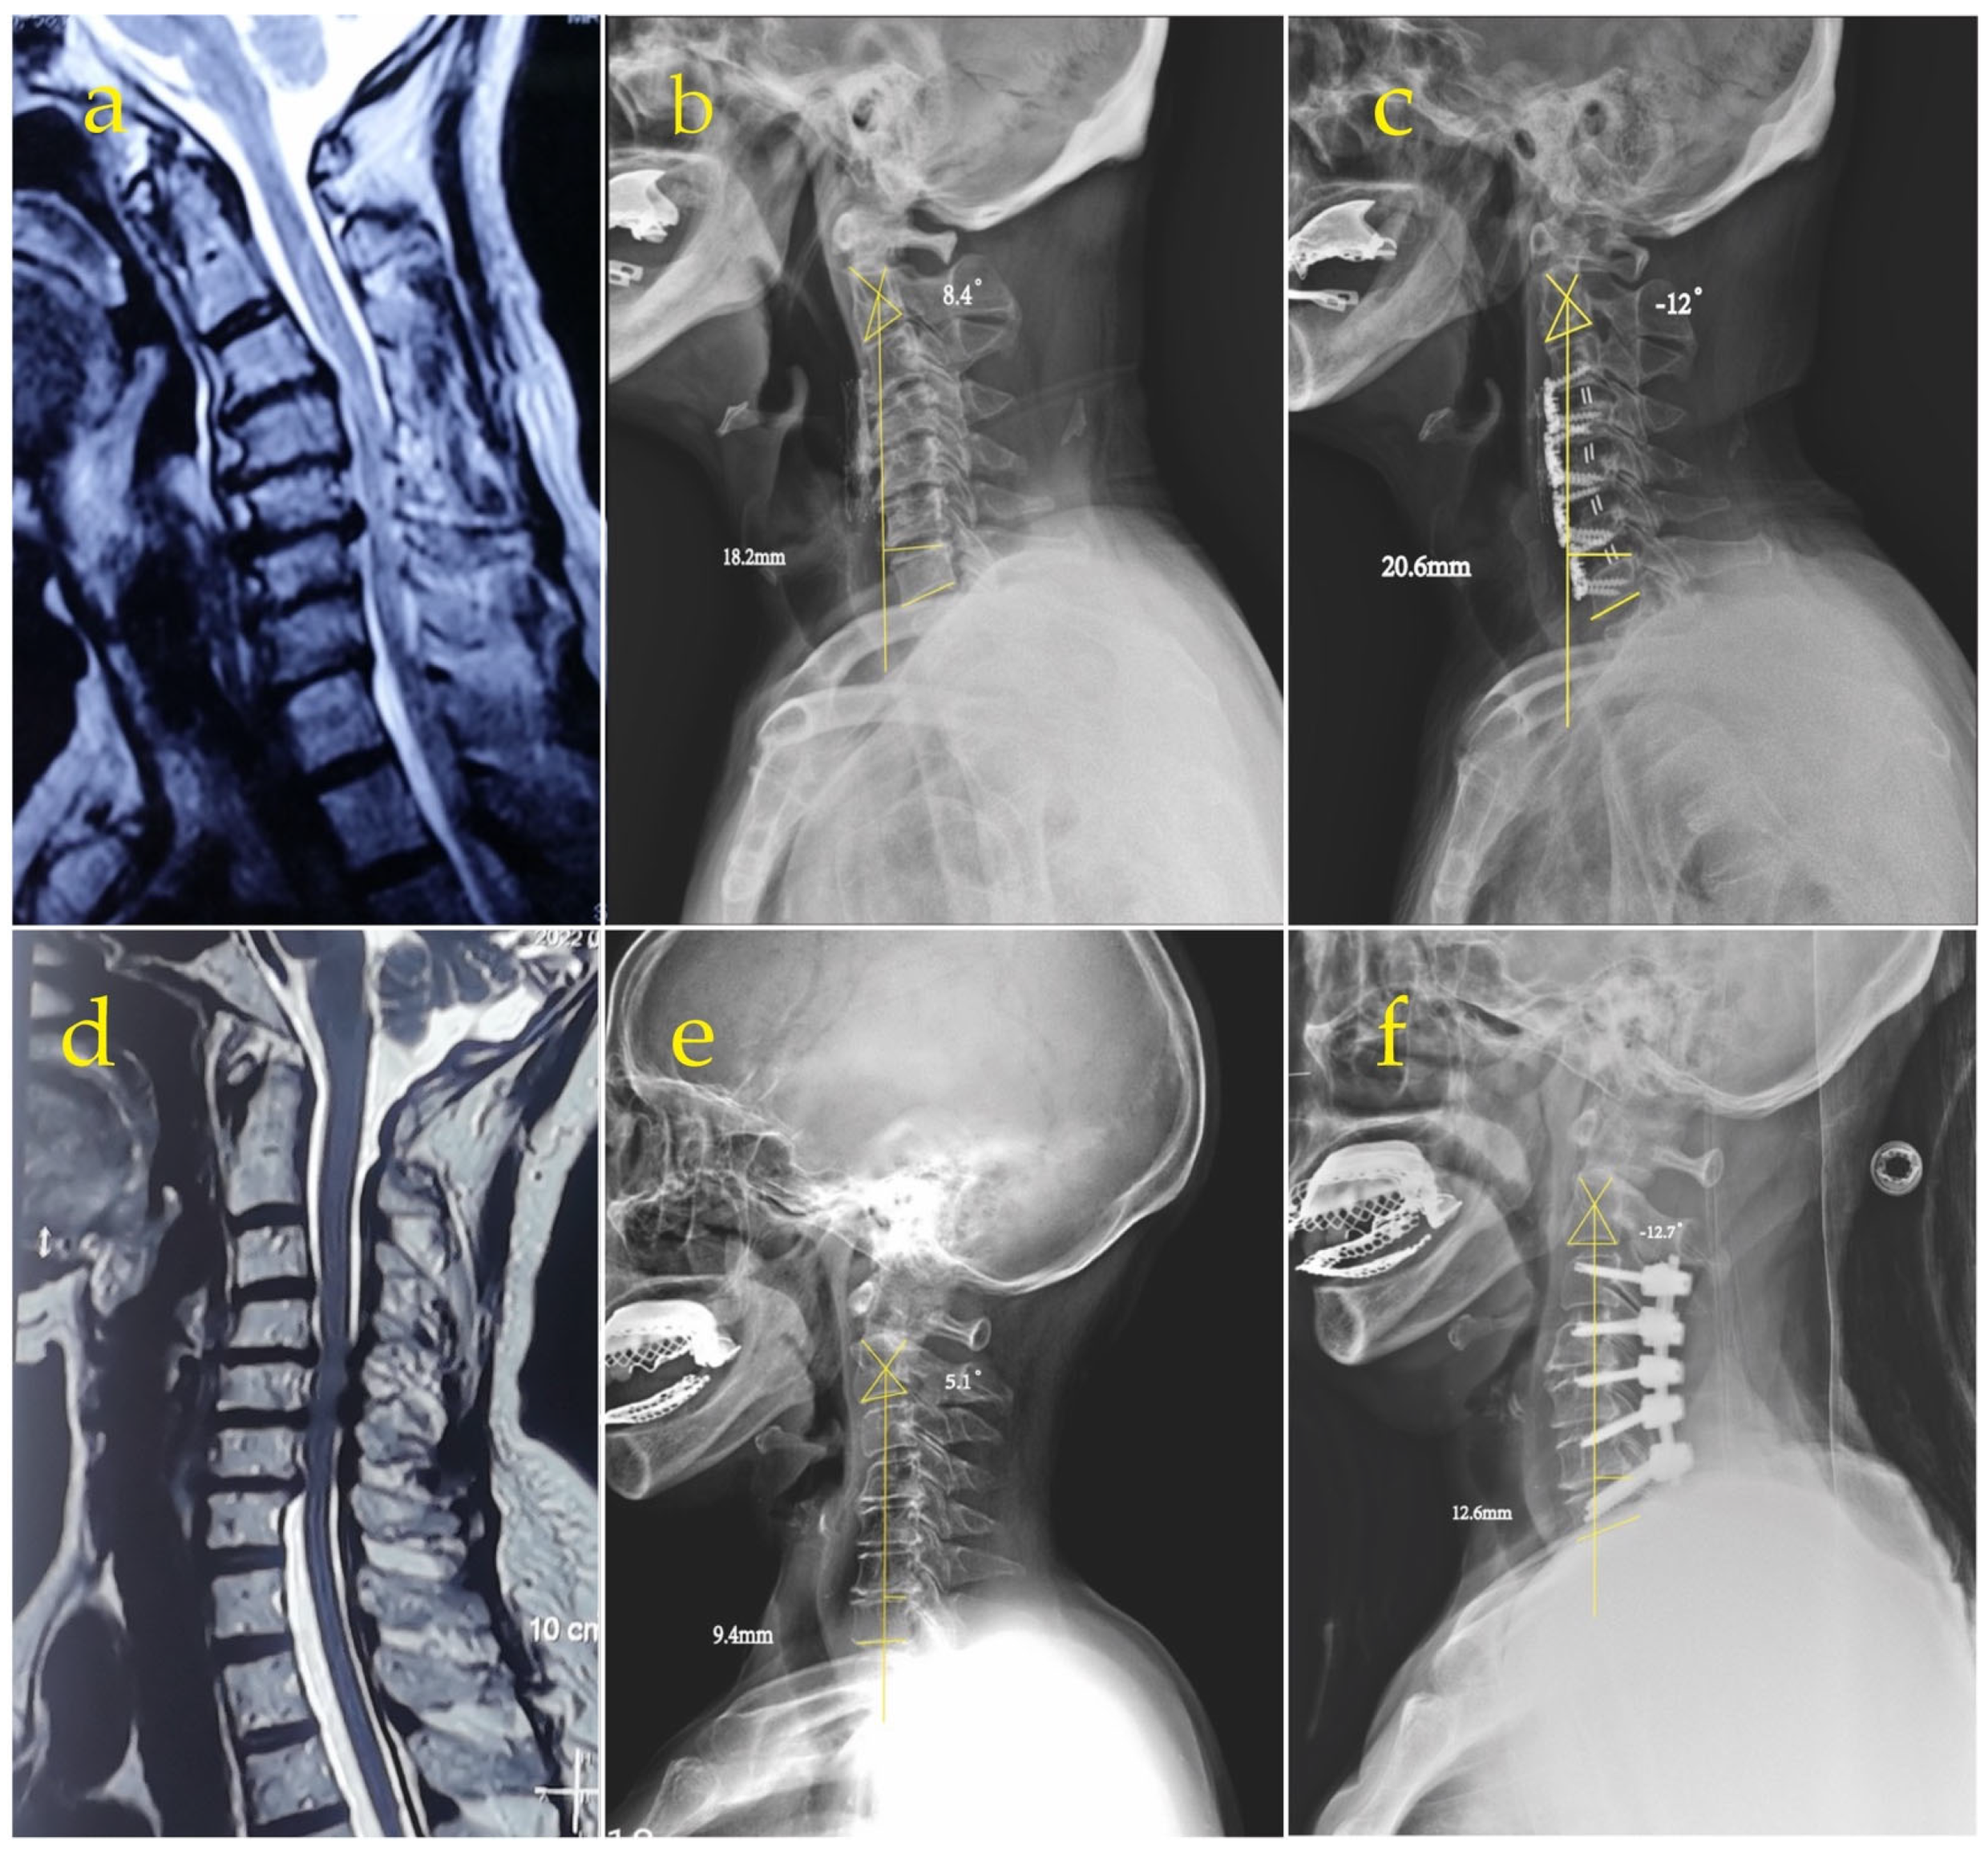

The average postoperative C2–7 cobb angle improved from 4.1° to −12.3° in the anterior group and from 3.8° to −12° in the posterior group, without significant differences between the groups (Table 3). At the final follow-up, the mean SVA increased from 14.8 mm to 19.0 mm in the anterior group and from 15.6 mm to 21.8 mm in the posterior group and was significantly different between the two groups (Table 3). Figure 2 shows the recovery of the patient’s cobb angle and the increase in SVA after the anterior and posterior surgeries.

Figure 2. (a) Preoperative MRI showing cervical spinal stenosis and myelopathy. The preoperative (b) and postoperative (c) plain films displayed that the anterior convexity of C2–7 was restored after anterior surgery and the SVA increased compared to preoperatively. (d) Preoperative MRI showing cervical spinal stenosis and myelopathy. The preoperative (e) and postoperative (f) plain films revealed that the anterior convexity of C2–7 was restored after posterior surgery and the SVA increased compared to preoperatively.